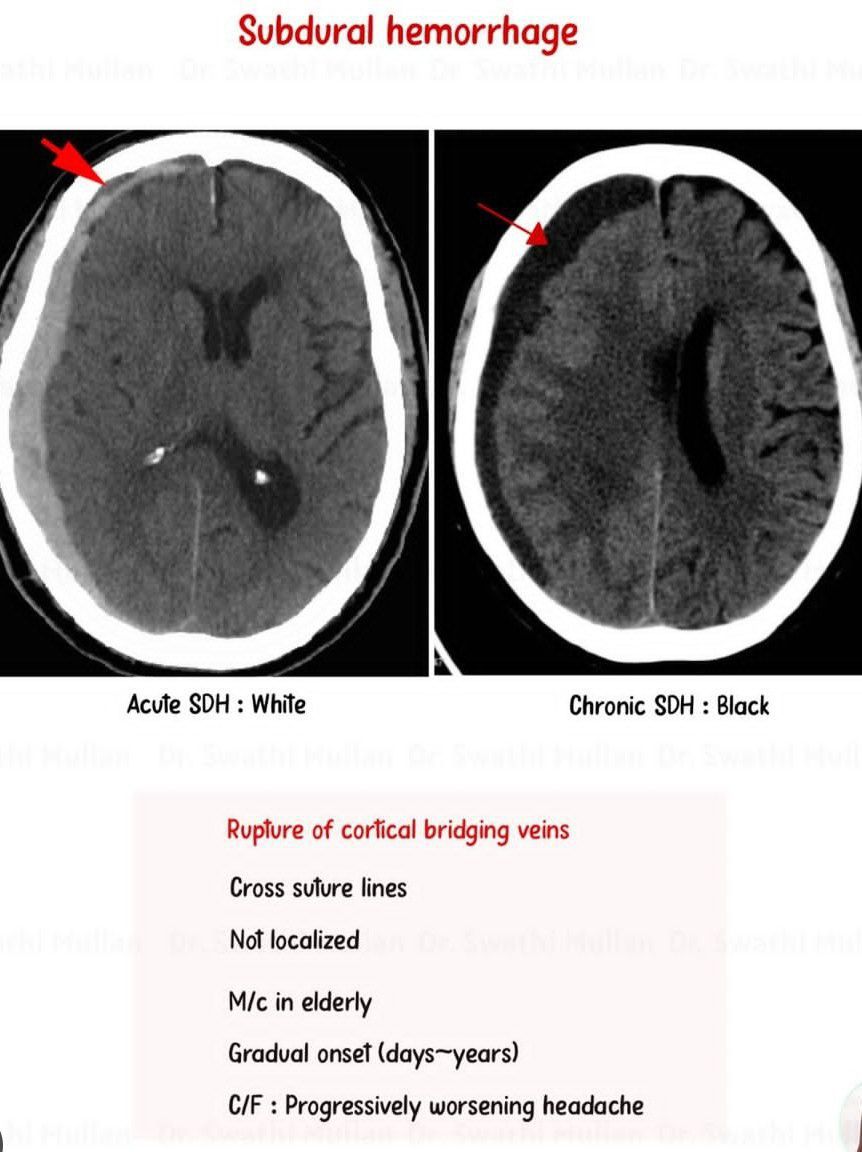

Subdural Hematoma